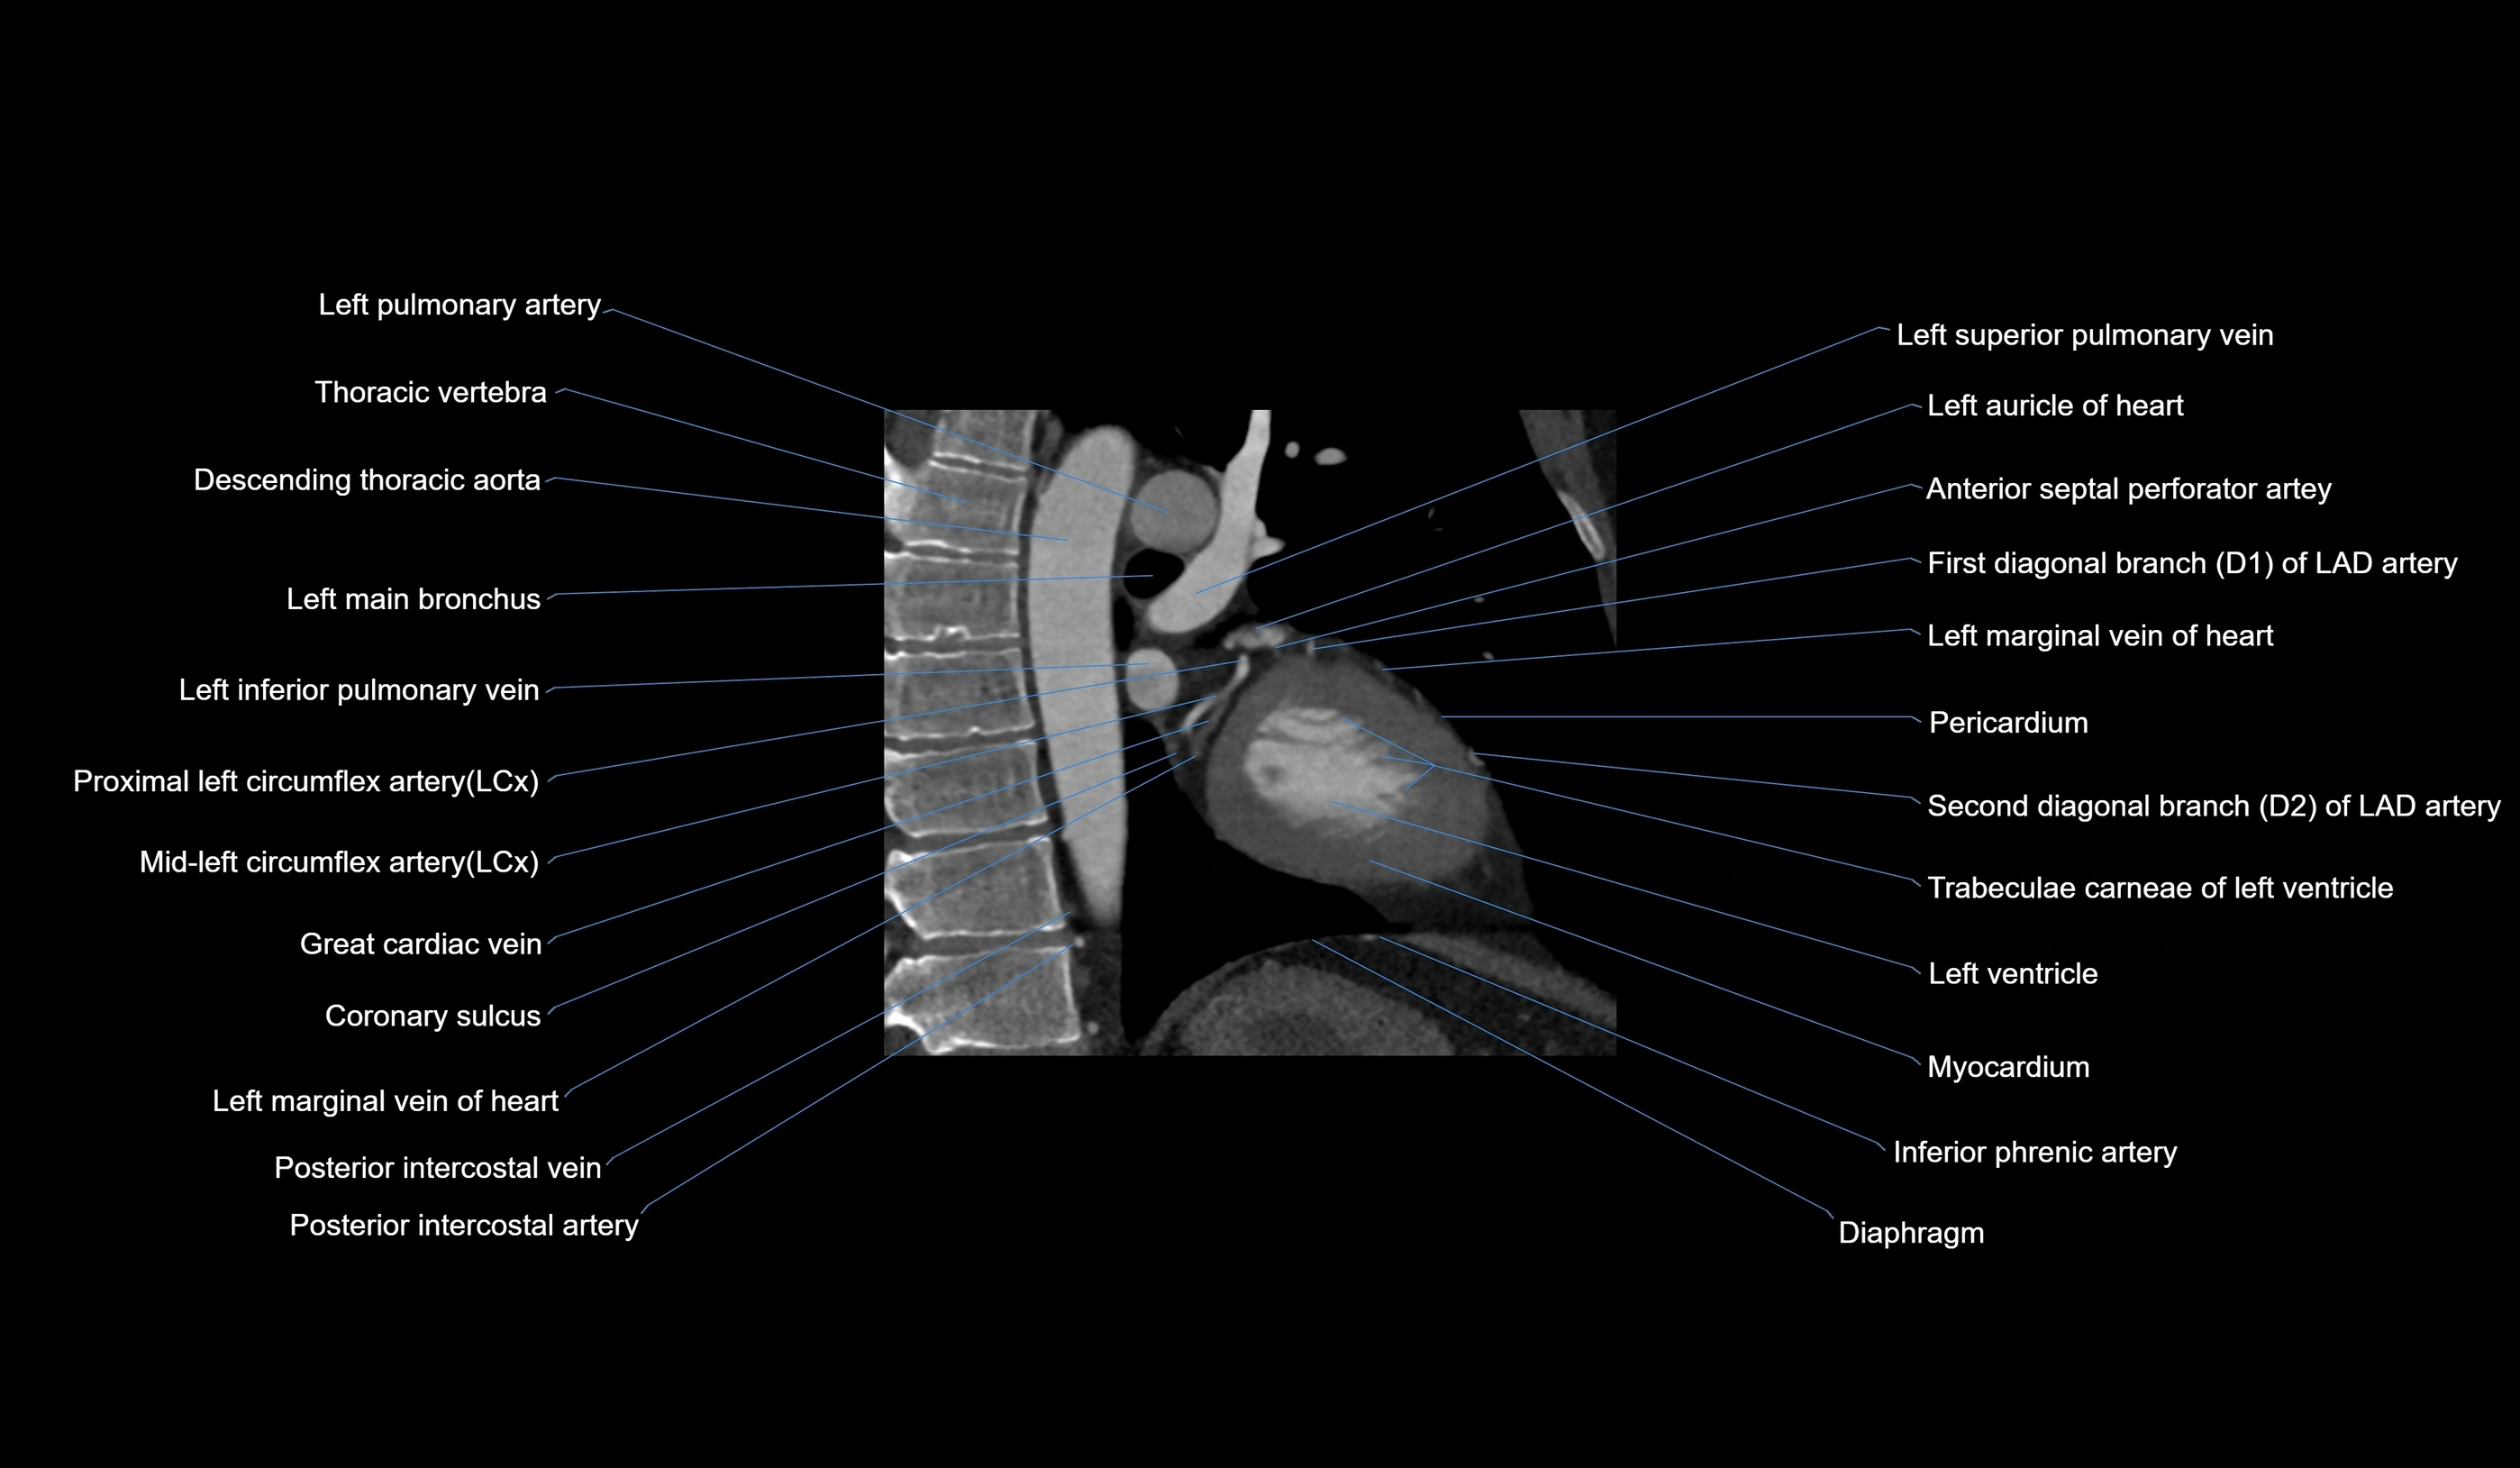

CT images